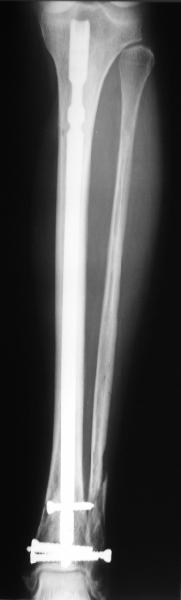

In delayed cases acute length restoration performed only in the tibia may leave the fibula shortened thus change the mortise. So it is reasonable to restore length of both bones simultaneously by distractor and fix the fibula not with open reduction and plating but just by a single perQ screw. Example attached.

I am just trying to illustrate that prevention of 1)tibial valgus and 2)loss of reduction can be provided without fibular plating. Small changes of conventional nailing techniques allow to maintain reduction of the tibia reliably without adjunctive fibular stabilization.